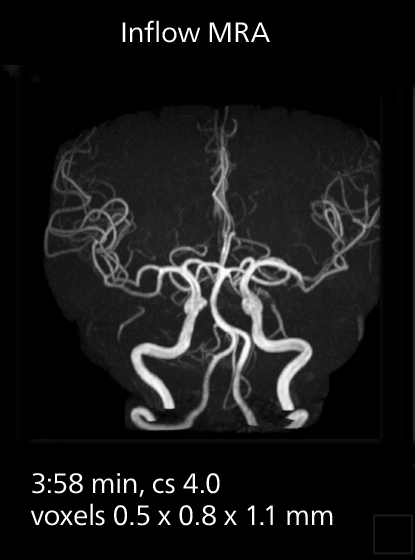

The value of the Elition X gradients is also evident in DWIBS studies. “The fact that we can consistently obtain distortion‐free DWIBS while reducing imaging time at three coronal stations is excellent,” Dr. Makuuchi says. “In these patients, it’s also important that the application of Compressed SENSE to T2‐weighted, STIR and mDIXON sequences has no impact on the examination time of whole‐body imaging. As a result of the increased speed and higher image quality we realize, DWIBS studies have now become routine examinations.”

Fast whole body DWIBS examination

With SmartPath to Elition X the team can obtain excellent quality DWIBS imaging and reduce imaging time. Other sequences also fit in the examination slot. This case shows left paravertebral neurogenic tumor and Th10 vertebral hemangiomas.